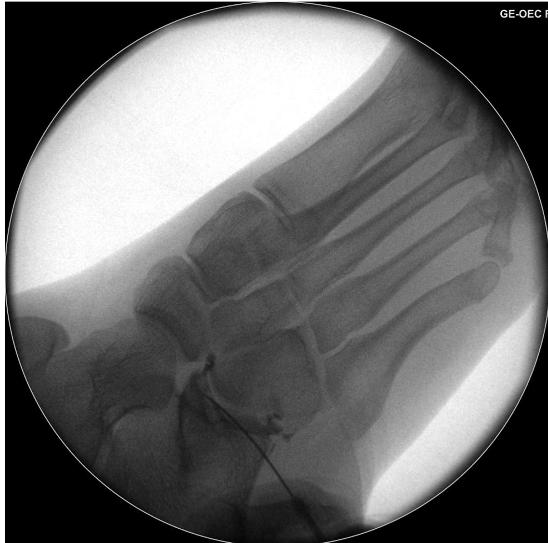

CMC-luxation kan ibland vara svår att se på slätröntgenröntgen. Skadan är ofta associerad med fraktur på hama tum och/eller metakarpalben. Man bör i sin distalstatusundersökning vara uppmärksam på ulnarisnervens funktion. Luxationen kan ibland reponeras slutet, men oftast krävs kirurgisk behandling med stiftning.

Perilunär luxation innebär en luxation mellan karpalben och lunatum. Missad skada slutar ofta med total handledsartrodes. För att upptäcka skadan på röntgen bör man leta efter oordning bland karpalbenen och avbrott i Gi lulas linjer som i normalfallet förlöper som två harmoniska bågar (se bild). Skadan framträder oftast tydligast på sidobilden med capitatums läge dorsalt beläget om lunatum. Obser vera medianusfunktionen och gör ett försök till sluten reposition. Patient en ska behandlas på operation med stiftning och ligamentsutur oavsett om repositionen lyckats eller ej.

Arvid von Konow Gilulas linjer ska löpa som två harmoniska bågar i carpallederna. Perilunär luxation ses oftast tydligast på sidobilden. Vid skada blir bågarna störda och svåra att följa. Vid Seymourfraktur genom fysen på distala falangen blir ofta nagelbädden nedslagen i frakturen.Läkning efter hälseneruptur sker i tre faser: